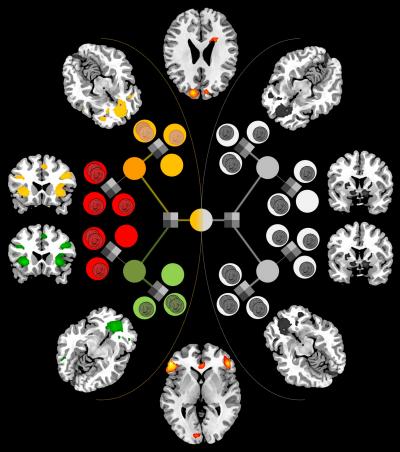

Researchers at the California Institute of Technology (Caltech) have, for the first time, pinpointed areas of the brain—the inferior lateral prefrontal cortex and frontopolar cortex—that seem to serve as this "arbitrator" between the two decision-making systems, weighing the reliability of the predictions each makes and then allocating control accordingly. The results appear in the current issue of the journal Neuron .

With the results from those tests in hand, the researchers were able to compare the fMRI data and choices made by the subjects against several computational models they constructed to account for behavior. The model that most accurately matched the experimental data involved the two brain systems making separate predictions about which action to take in a given situation. Receiving signals from those systems, the arbitrator kept track of the reliability of the predictions by measuring the difference between the predicted and actual outcomes for each system. It then used those reliability estimates to determine how much control each system should exert over the individual's behavior. In this model, the arbitrator ensures that the system making the most reliable predictions at any moment exerts the greatest degree of control over behavior.

In line with previous findings from the O'Doherty lab and elsewhere, the researchers saw in the brain scans that an area known as the posterior putamen was active at times when the model predicted that the habitual system should be calculating prediction values. Going a step further, they examined the connectivity between the posterior putamen and the arbitrator. What they found might explain how the arbitrator sets the weight for the two learning systems: the connection between the arbitrator area and the posterior putamen changed according to whether the goal-directed or habitual system was deemed to be more reliable. However, no such connection effects were found between the arbitrator and brain regions involved in goal-directed learning. This suggests that the arbitrator may work mainly by modulating the activity of the habitual system.